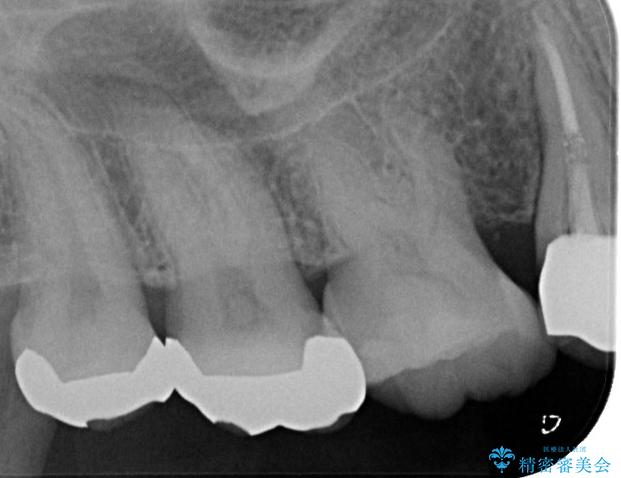

精密検査をしたところ、該当の歯に歯根破折を認めました。

本症例では、抜歯、インプラント埋入、骨補填材を填入し仮歯を装着するまでを1日で終わらせる1Dayインプラントを行いました。